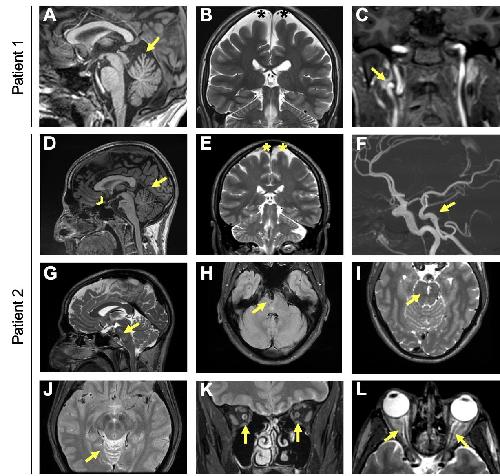

Figure 1 Multimodal imaging of the patients. Patient 1: (A) Color fundus photograph showing pallor of the optic nerve head and reduced caliber of the retinal vessels. Note the abnormal visibility of the choroidal vessels due to RPE damage in the midperiphery. (B) Short-wavelength fundus autofluorescence (SW-FAF) showing a parafoveal ring characteristic of RP (white arrows). (C) SD-OCT macular scan showing preserved segmentation in the foveal area with peripheral loss of the ellipsoidal zone (EZ) line nasal to the fovea (white arrow). Patient 2: (D) Color fundus photograph showing increased choroidal visibility beyond the temporal vascular arcades. Inset: pigment accumulation in the superior retinal periphery. (E) SW-FAF showing a relatively preserved intensity within the macular region and loss of the signal beyond the temporal vascular arcades. An incomplete hyperautofluorescent ring is visible in the temporal parafoveal region (yellow arrow). (F) SD-OCT scan along the horizontal meridian through the fovea showing preservation of retinal layers in the central macula and gradual disappearance of photoreceptor layers with increasing eccentricity in the temporal direction. The white arrow indicates the beginning of the disappearance of the EZ line. Patient 3: (G and H) Color fundus imaging of both eyes showing peripheral retinal bone spicules (blue arrows), papillary pallor, and evident atrophy of the RPE-choriocapillaris complex except in the macular area (delineated by white arrows). (I) SD-OCT macular scan showing an EZ line only visible beneath the fovea (between white arrows). |

Figure 1. Multimodal imaging of the patients.Patient 1: (A) Color fundus photograph showing pallor of the optic nerve head and reduced caliber of the retinal vessels. Note the abnormal visibility of the choroidal vessels due to RPE damage in the midperiphery. (B) Short-wavelength fundus autofluorescence (SW-FAF) showing a parafoveal ring characteristic of RP (white arrows). (C) SD-OCT macular scan showing preserved segmentation in the foveal area with peripheral loss of the ellipsoidal zone (EZ) line nasal to the fovea (white arrow). Patient 2: (D) Color fundus photograph showing increased choroidal visibility beyond the temporal vascular arcades. Inset: pigment accumulation in the superior retinal periphery. (E) SW-FAF showing a relatively preserved intensity within the macular region and loss of the signal beyond the temporal vascular arcades. An incomplete hyperautofluorescent ring is visible in the temporal parafoveal region (yellow arrow). (F) SD-OCT scan along the horizontal meridian through the fovea showing preservation of retinal layers in the central macula and gradual disappearance of photoreceptor layers with increasing eccentricity in the temporal direction. The white arrow indicates the beginning of the disappearance of the EZ line. Patient 3: (G and H) Color fundus imaging of both eyes showing peripheral retinal bone spicules (blue arrows), papillary pallor, and evident atrophy of the RPE-choriocapillaris complex except in the macular area (delineated by white arrows). (I) SD-OCT macular scan showing an EZ line only visible beneath the fovea (between white arrows). |